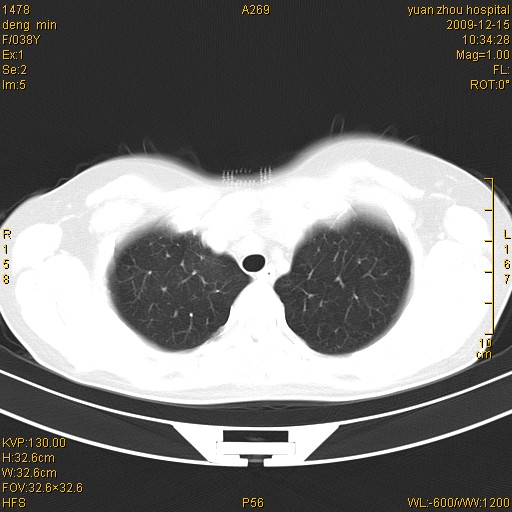

标题: CT23919:F38Y 咳嗽月余 [打印本页]

标题: CT23919:F38Y 咳嗽月余

右肺中下叶、左肺上叶舌段及左肺下叶支气管扩张合并感染。